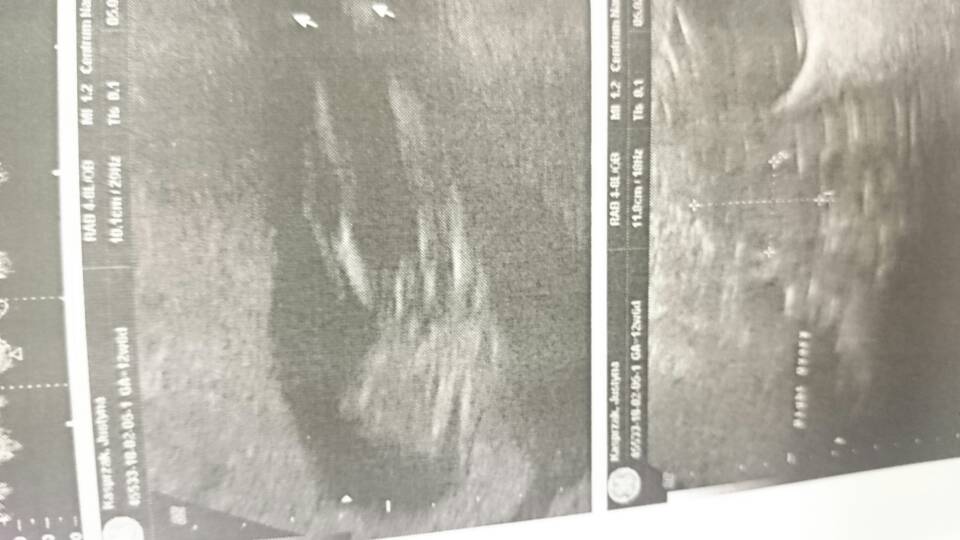

Już po badaniu :) wszystko jest dobrze, dzieciątko zdrowe, ale Pani doktor nie chciała podać mi płci :( [emoji12] jednak ja tam swoje widzę,co Wy na to

DSC_0362.JPG